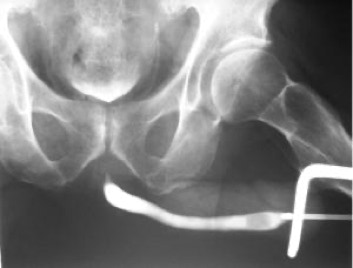

- Röntgendiagnostik des Harntraktes (in Kooperationspraxis)